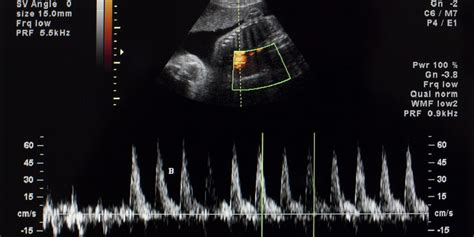

I Doppler fetali, noti anche come monitor per il battito cardiaco fetale, sono dispositivi che permettono di ascoltare e monitorare il cuore del bambino. Il loro funzionamento si basa su un principio simile a quello di un macchinario per ecografie in un ambulatorio medico o in ospedale. Nello specifico, apparecchi come il "Cuore di Bimbo" (AngelSounds) sfruttano l'effetto Doppler ad ultrasuoni a una potenza estremamente bassa.

È importante chiarire un aspetto tecnico fondamentale: il dispositivo non riproduce il "suono" diretto del cuore, ma un'amplificazione della differenza di frequenza tra l'ultrasuono emesso e l'ultrasuono che ritorna alla sonda, ovvero l'effetto Doppler. Quel rumore ritmico, che assomiglia al galoppo di un cavallo, è la trasposizione acustica di questo fenomeno fisico.